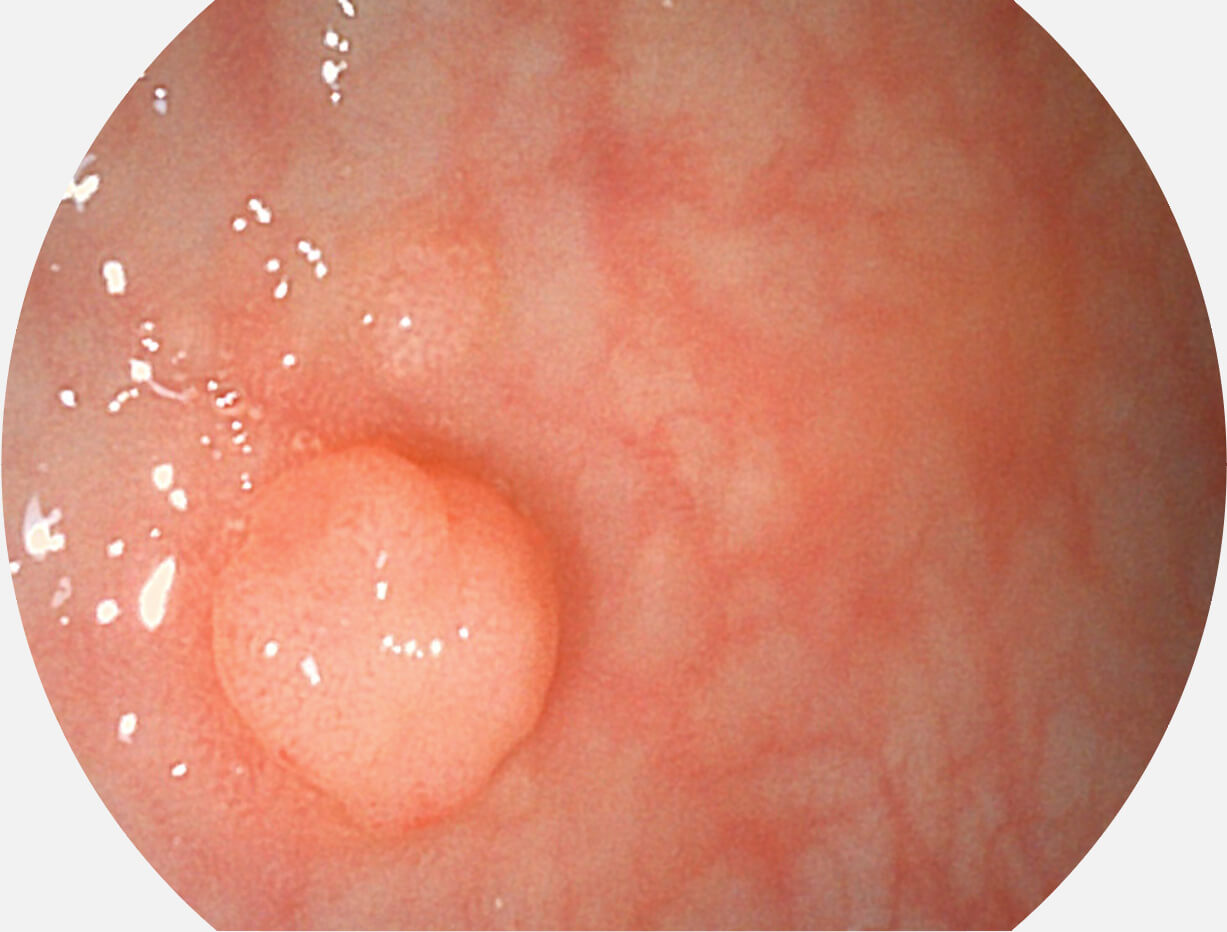

白光图像

白光图像

VIST图像

VIST图像

白光图像

白光图像

VIST图像

VIST图像

白光图像

白光图像

VIST图像

VIST图像